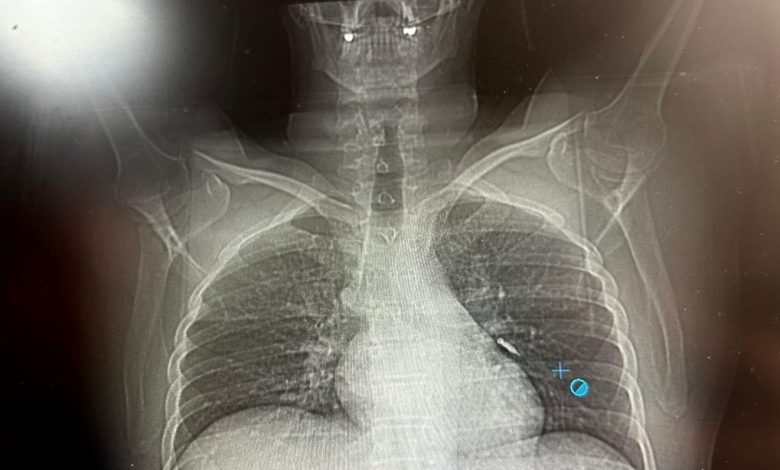

Van‘ın İpekyolu ilçesinde ikamet eden F.T. isimli hasta, dış merkezli bir diş kliniğinde implant tedavisi gördüğü sırada, implant vidası yanlışlıkla soluk borusuna kaçtı.

Nefes borusuna kaçan vida nedeniyle hasta, ileri tetkik ve tedavi amacıyla Van Eğitim ve Araştırma Hastanesi’ne sevk edildi.

Hastaya bronkoskopi işlemi uygulandı. Sol akciğerin üst lobunda saplanmış şekilde tespit edilen vida, vidalı yapısı ve bulunduğu konum nedeniyle güçlükle yerinden oynatılabildi.

Yapılan uzun ve titiz müdahale sonrası vida yerinden çıkarılamasa da hasta bir süre sonra geçirdiği öksürükle birlikte implant vidasını midesine gönderdi. Vida, daha sonra doğal yollarla vücuttan atıldı.